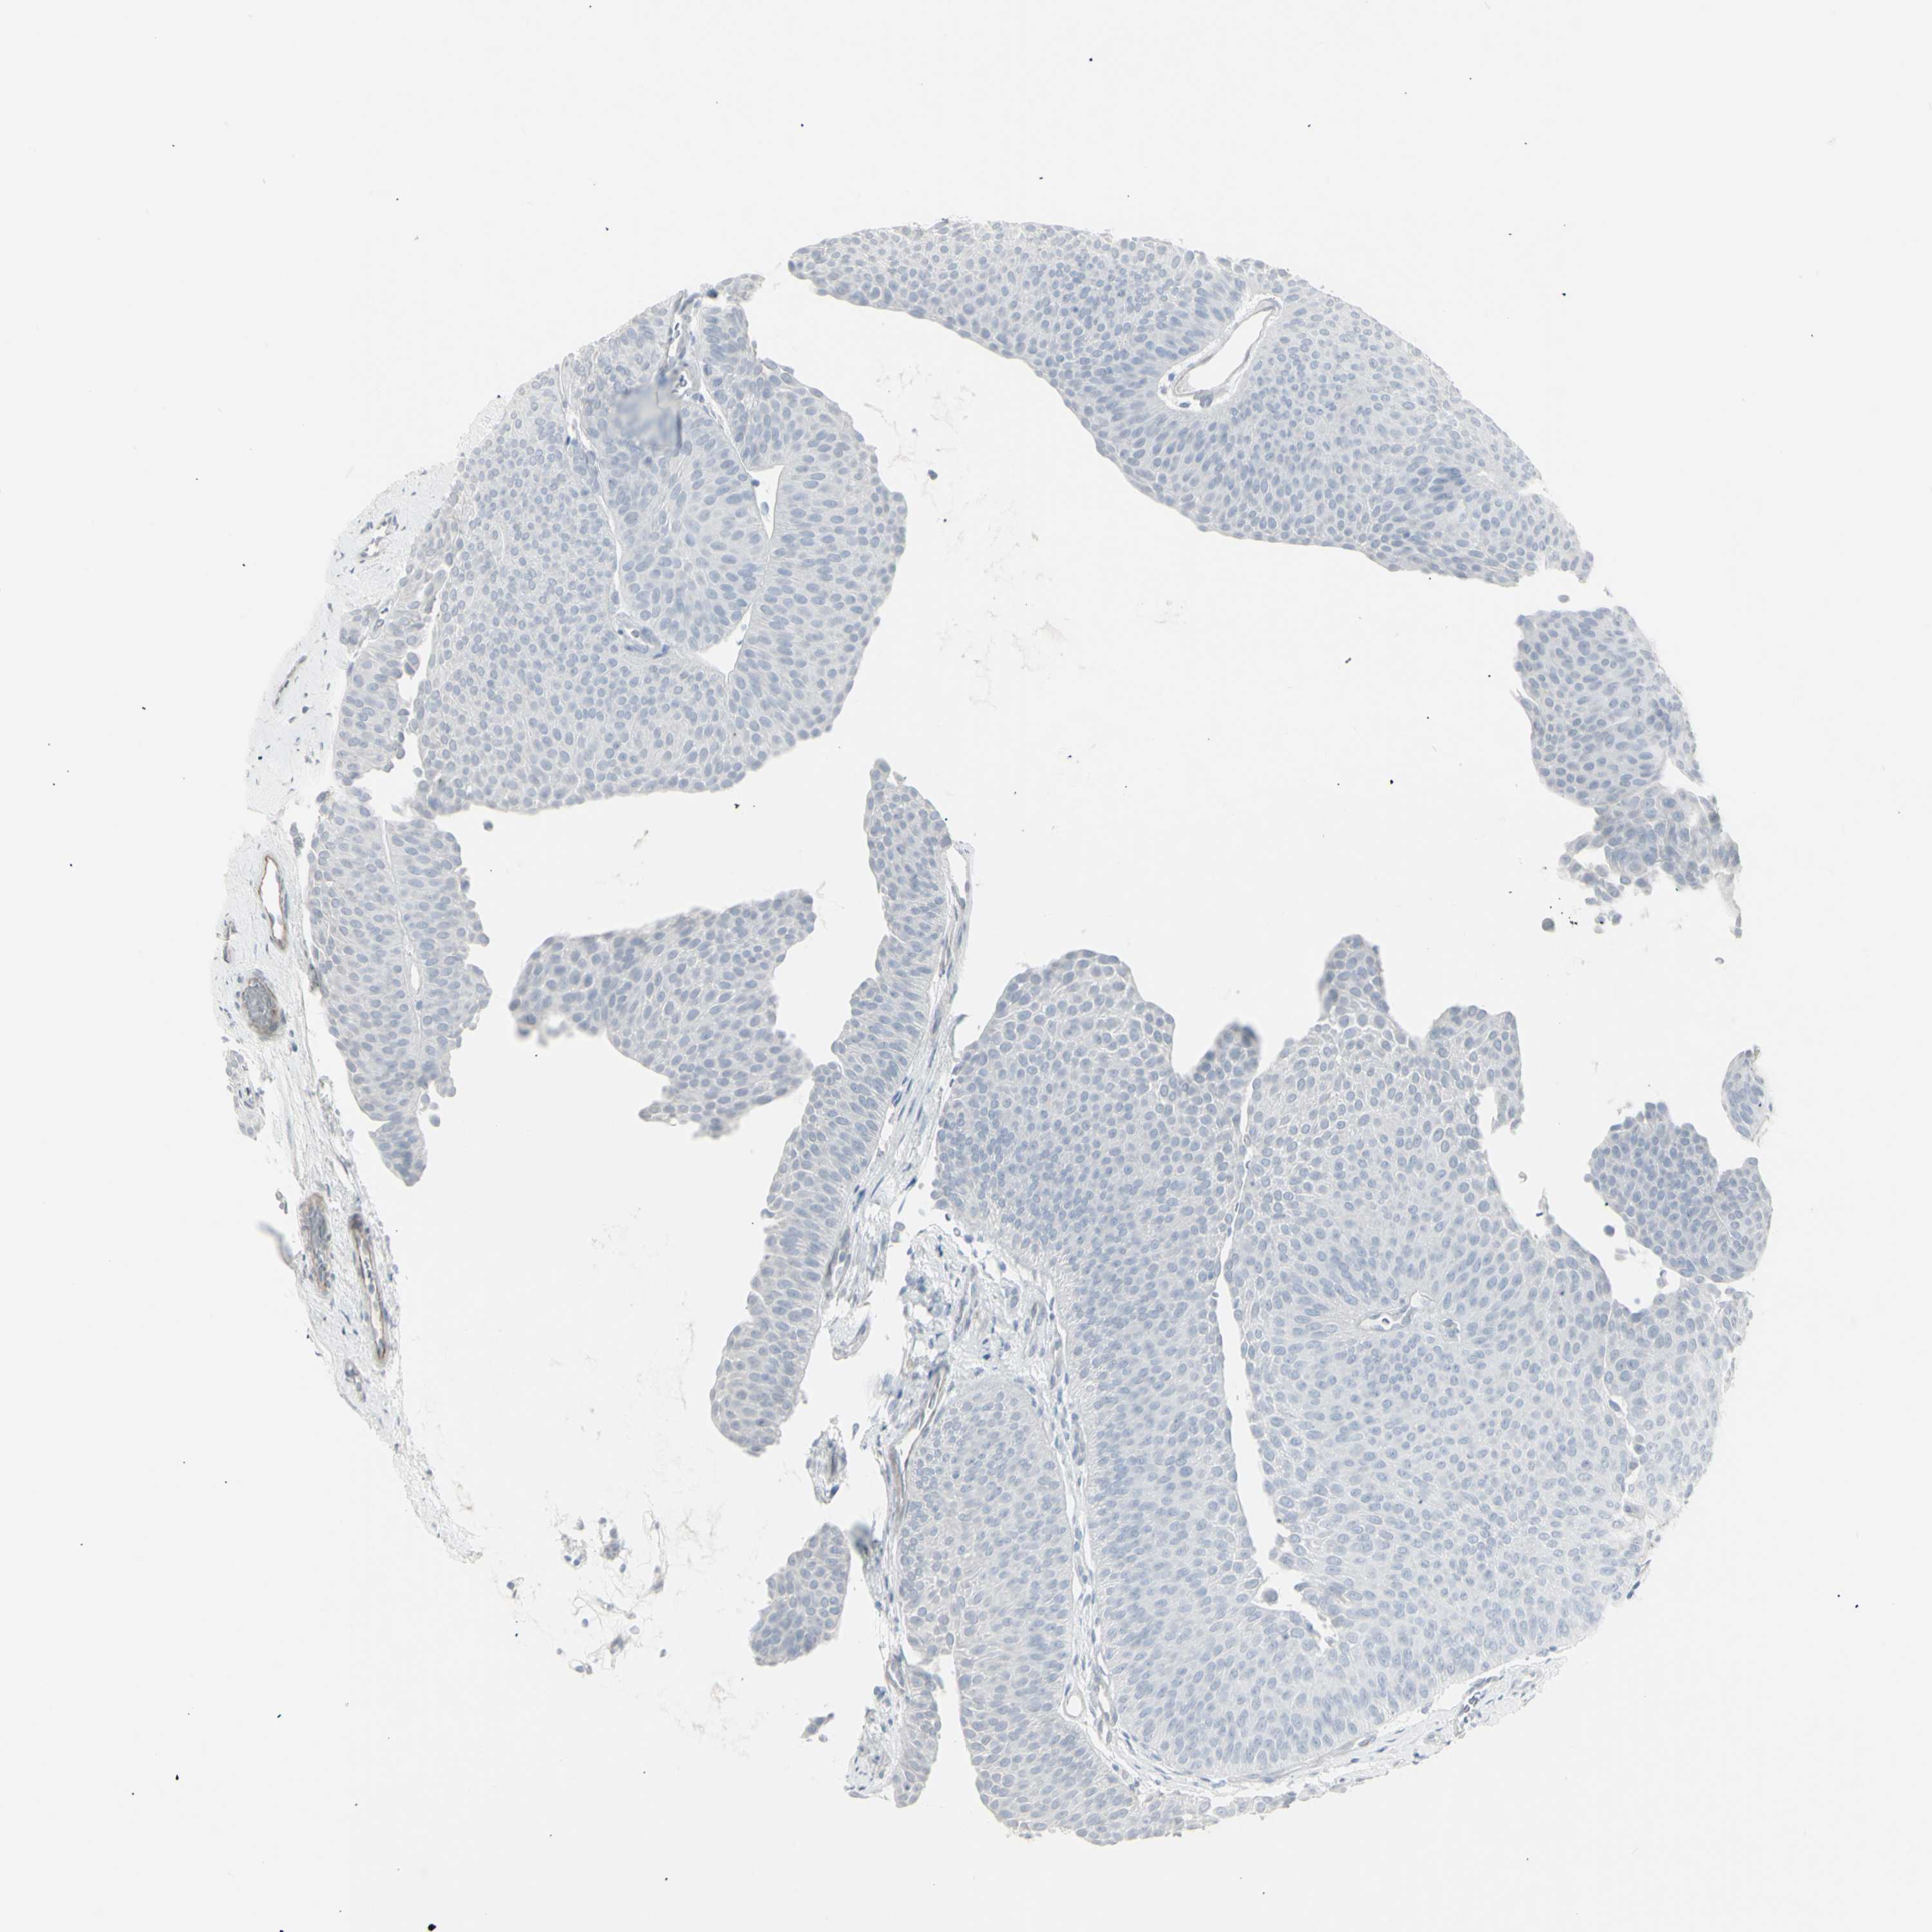

UROTHELIAL CANCER - Protein expressioni

A mouse-over function shows sample information and annotation data. Click on an image to view it in a full screen mode. Samples can be filtered based on level of antibody staining by selecting one or several of the following categories: high, medium, low and not detected. The assay and annotation is described here.

Antibody stainingi

Antibody staining in the annotated cell types in the current human tissue is reported as not detected, low, medium, or high, based on conventional immunohistochemistry profiling in selected tissues. This score is based on the combination of the staining intensity and fraction of stained cells.

Each image is clickable and will lead to virtual microscopy that enables deeper exploration of all samples and also displays staining intensity scores, fraction scores and subcellular localization as well as patient and tissue information for each sample.

Antibody HPA053904

Antibody HPA056744

Antibody CAB012332

Staining

High

Medium

Low

Not detected

Intensity

Strong

Moderate

Weak

Negative

Quantity

>75%

75%-25%

<25%

None

Location

Nuclear

Cytoplasmic/membranous

Cytoplasmic/membranous,nuclear

Urothelial carcinoma, High grade

Urothelial carcinoma, NOS

Urothelial carcinoma, Low grade